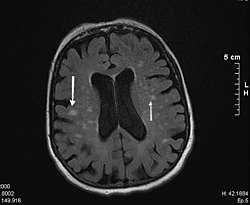

Bild einer Magnetresonanztomographie

Die Diagnose wird mit einer MRT (Magnetresonanztomographie = Kernspintomographie) gesichert. Diese zeigt in den T2-gewichteten Bildern typische weißliche konfluierende Herde um die Ventrikel und besonders an den vorderen und hinteren Enden der Seitenventrikel eine kappenartige Sklerosezone.